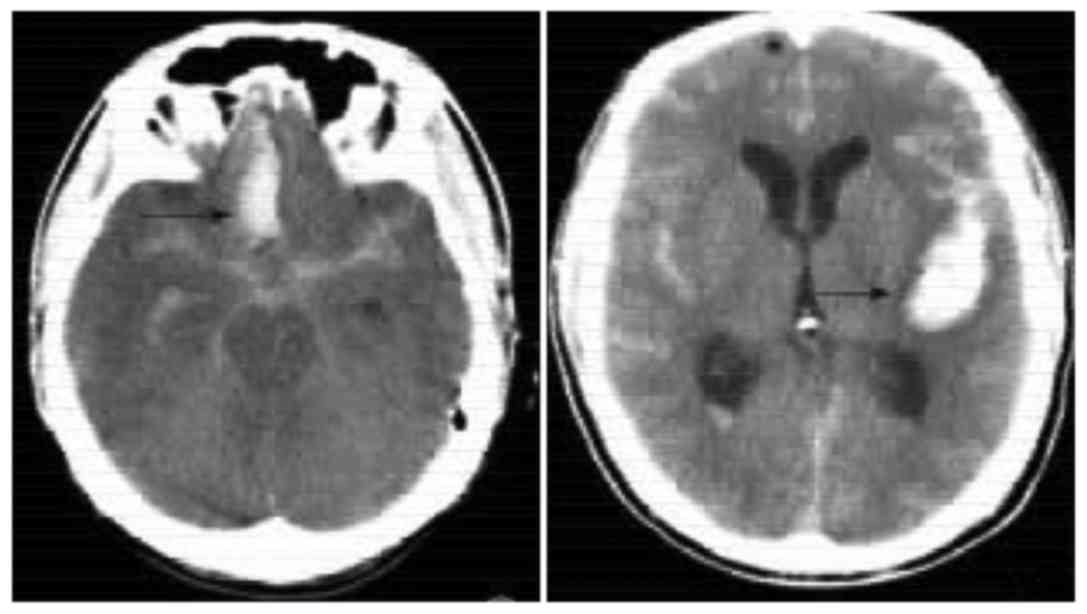

Figure 1.

Representative images of SAH with a CT scan. SAH, subarachnoid hemorrhage.